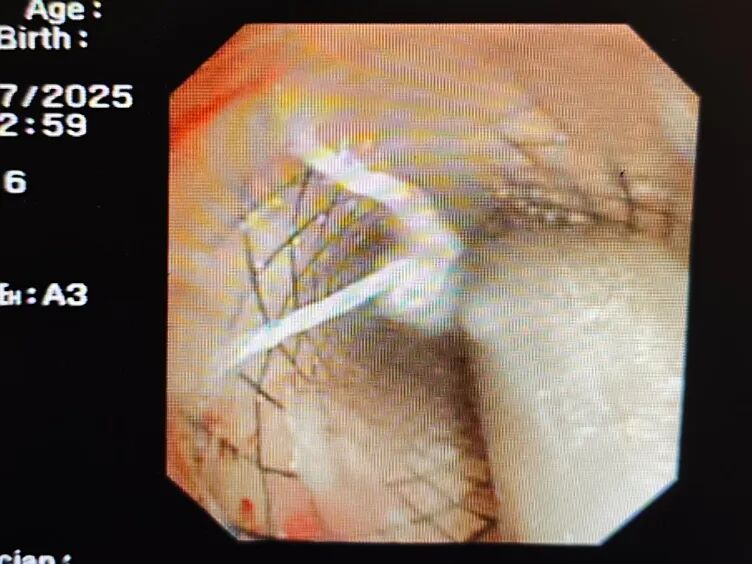

术中,呼吸与危重症医学科与耳鼻咽喉科、麻醉科密切配合:麻醉科采用保留患者自主呼吸静脉麻醉,插入支气管镜后,清晰找到气切口下约2cm处膜部瘘口,大小约12*6mm;置入斑马导丝精准定位;取出原有金属气切套管后,沿导丝顺利植入直径18mm、长度40mm的金属覆膜支架;反复调整位置确认瘘口完全封堵,最后重新置入7号金属气切套管。

IMG_20250709_214044.jpg

全程用时1小时,微创操作几乎无出血,阿婆术中生命体征平稳,最终顺利康复出院。